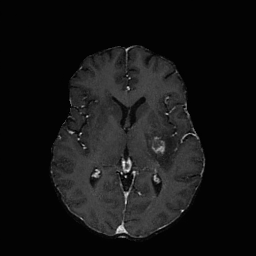

| non-CE T1w (Input) | Residual U-Net (PM) | RF Baseline | PMRF (ours) | CE T1w (GT) |

We qualitatively evaluate the top-performing Residual U-Net (Posterior Mean), RF baseline, and PMRF models (with a patch-overlap of 32 for all and integration steps for the RF baseline as well as the PMRF model) on the held-out test set. For a set of representative cases, Figure 3 compares the non-CE T1w input, Res. U-Net (equivalent to PM), RF baseline, our two-stage PMRF, and the ground truth CE T1w image. Example 1 depicts a metastases patient, example 2 a high-grade glioma patient, and example 3 a meningioma patient. Across these test cases, the Res. U-Net output accurately localizes lesions and captures their overall enhancement intensity but appears overly smooth, and muted in rim heterogeneity and fine texture. The Stage 2 PMRF refinement consistently sharpens lesion boundaries, reinstates subtle vascular and margin details, and restores characteristic enhancement patterns, yielding synthetic images nearly indistinguishable from true post-contrast scans. However, Stage 2 can only refine what the posterior-mean predictor already suggests. If a subtle rim, micro-metastasis, or vessel enhancement is entirely suppressed in Stage 1, Stage 2 has no signal to resurrect it; its perturbations stay within a narrow neighborhood of the Stage 1 output. In contrast, the RF baseline directly predicts the CE signal from the perturbed non-CE image. However, this comes with the limitation of not predicting the CE strength faithful or missing subtle details as in examples 2 and 3.